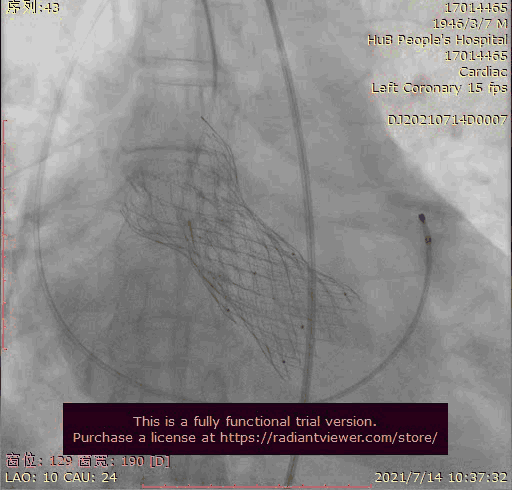

奇思妙想使用射频消融大头压住支架至窦底

在大头压迫支架下释放第二个瓣膜

第二个支架完美释放固定第一个支架

术后基本无返流

3.第三次释放瓣膜后位置的把控非常精准,瓣膜位置合适,但由于稳定性差,撤出输送系统时瓣膜跳至窦上,此时非常凶险,瓣膜无法固定住,受到血流的冲击,可能对升主造成夹层的风险,一般会选择开胸取出,但风险非常,在江洪教授的思考下和团队的讨论下,决定使用射频消融大头穿过支架网孔使瓣膜到窦底固定,在此基础上释放第二个瓣膜,使用第二个瓣膜花冠固定住第一个瓣膜

4.第四次瓣膜释放后两个瓣膜均稳定住,造影超声评估无瓣周漏,二尖瓣反流也基本消失,观察一小时后,无其他情况。患者顺利下台